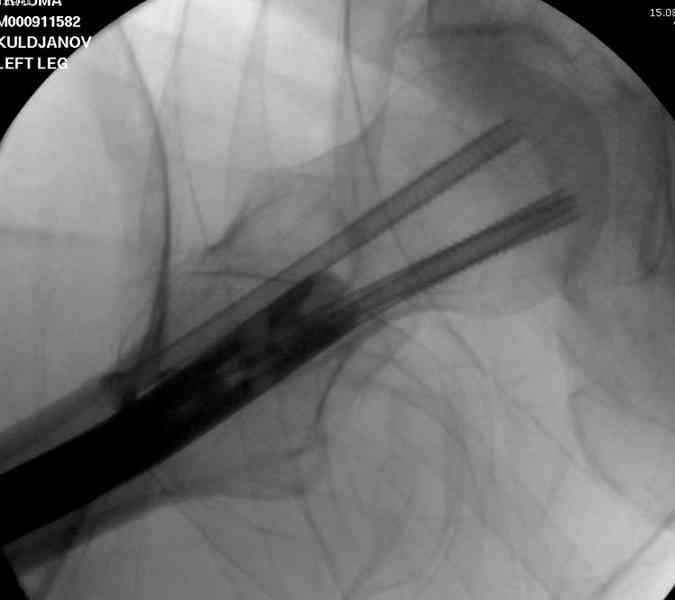

В операционной спереди гвоздя провел два 6.5 мм каннулированных шурупа, также через проксимальное отверстие антеградного гвоздя удалось провести шуруп.

Здесь представлены снимки больного 65 лет, поступившего с диагнозом перелом

бедра после автоаварии.

В первый же день произведено антеградное штифтованием DePuy Trochanteric Nail.

На второй день (7) обнаружен пропущенный перелом,

и проведены шурурпы через и спереди штифта без удаления.

Послеоперационные снимки